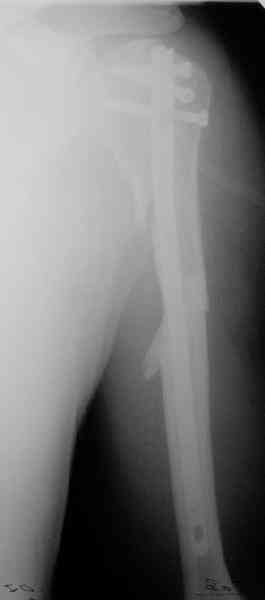

Попытка закрыто изменить положение не удалась. Передним доступом сделали открытую репозицию, гленоид без особенностей. Временно фиксировали спицами и остроконечным костедержателем. Фиксировали гвоздем T2 PHN (Stryker). Для профилактики вывихов после введения проксимальных винтов ротировали дистальный отдел кнаружи на 30

градусов как аналог остеотомии по Weber. Снимки в приложении. Комментарии и критика привествуются.

Attempt of closed reduction failed. Open reduction via anterior approach. The head was temporarily fixed by wires and sharp clamps. Fixation by a nail - T2 PHN (Stryker). The distal fragment has been rotated 30 degrees externally after proximal locking for dislocation prevention as "virtual" Weber osteotomy. Images attached.

Comments/critics are welcome.

All 3 screws are in the head. The feature of the nail is that it has four holes oriented not 45 degrees to frontal or sagittal planr, but anatomically to the head and both tubercles. The holes in the nail are threaded so angular stability is perfect, and contain a nylon bushing

preventing any screw rotation/back out.